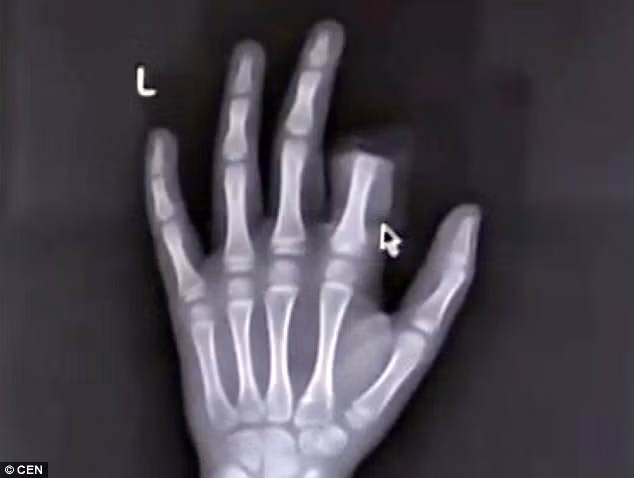

| Peng và hình ảnh chụp X-quang cho thấy đốt ngón tay trỏ đã hoàn toàn bị cắt rời. |